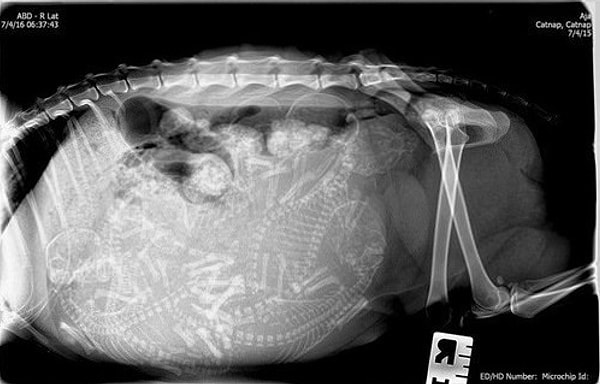

5. Кошка

6. Снова кошка